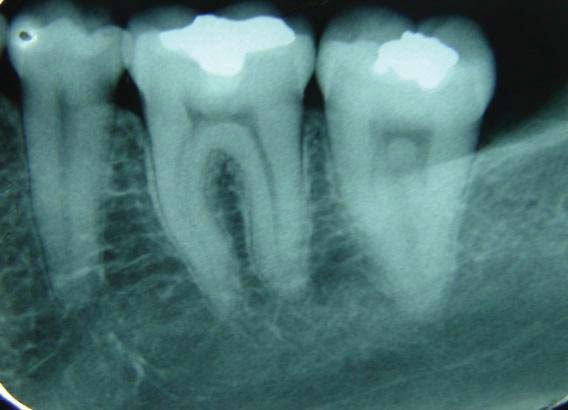

Clinical examination revealed two Class I amalgam restorations in mandibular first molar, one in the central sulcus and the other in the buccal sulcus (Figures 1 and 2). They appeared to be secondary carious lesions and were classified as clinically unsatisfactory. According to the patient, sensitivity to hot and cold had started five months before and the restoration was made 18 years earlier. There were two pigmented cracks, one on the buccal (Figures 1 and 2) and the other on the lingual surface. Occlusal contacts were checked with articulating paper and revealed a larger contact area on the occlusal surface than in other areas. Periapical and interproximal radiographs did not suggest the presence of a crack (Figure 3). Was performed tooth percussion and pulp vitality test with cold air and the patient responded with sensitivity.